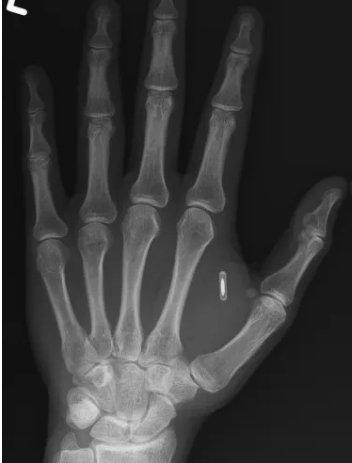

ABD'nin Missouri eyaletinde yaşayan bir sihirbaz ve moleküler biyolog, yıllar önce eğlence amacıyla eline yerleştirdiği mikroçip nedeniyle ilginç bir sorunla karşı karşıya kaldı. Sahne adı "Zi the Mentalist" olan Zi Teng Wang, Facebook'ta yaptığı paylaşımda, çipin şifresini unuttuğunu ve bu nedenle kendi bedenindeki teknolojiye erişemediğini duyurdu. Wang, gönderisine başparmağı ile işaret parmağı arasında duran mikroçipi gösteren röntgen görüntüsünü de ekledi.

SİHİR NUMARASI İÇİN YAPTIRMIŞTIWang, RFID olarak bilinen bu küçük cihazı yıllar önce sahne gösterilerinde kullanmak üzere eline yerleştirdiğini belirtti. Seyircilerin telefonlarını eline yaklaştırmasıyla tetiklenen efekti "gizemli" bir illüzyon olarak tasarlamıştı. Ancak izleyicilerin telefonlarını defalarca eline bastırmak zorunda kalması, beklediği büyülü etkiyi yaratmadı. Üstelik birçok kişinin telefonunda RFID okuyucusu aktif de değildi. Kendi telefonunu kullanmak ise numaranın tüm etkisini kaybediyordu.

Gösterilerde istediği sonucu alamayan Wang, daha sonra çipi bir Bitcoin adresine yönlendirecek şekilde yeniden programladı ve Imgur'da bir meme görseline bağladı. Fakat birkaç yıl önce Imgur bağlantısının çökmesi üzerine çipi tekrar programlamak istedi. İşte bu noktada gerçek sorun ortaya çıktı: Şifreyi tamamen unutmuştu.